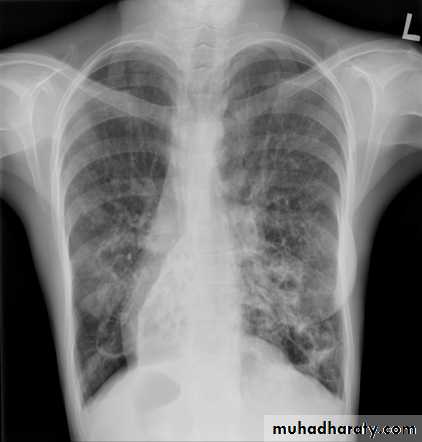

Radiology

Chest x-rayHyperlucency

Vascular attenuationHyperinflation (emphysema).

Radiology:CXR

Mild disease – normal XRC

Advanced disease – cysts + fluid levels

peribronchial thickening, “tram tracks”, “ring shadows”